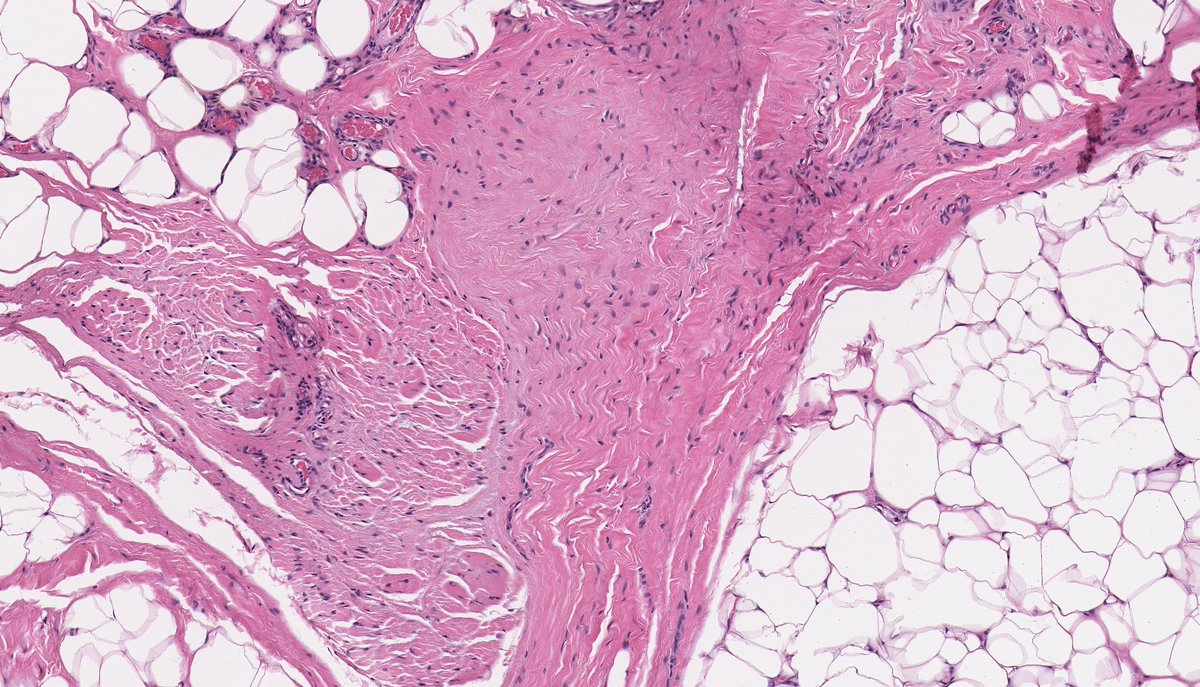

Anatomical Pathologist - UBC #BSTpath #GYNpath